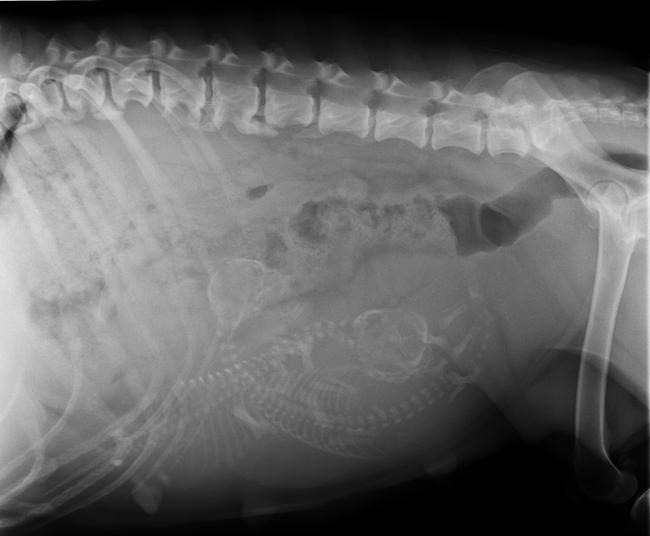

Ik heb de DA gebelt,en aangezien er geen echo gemaakt is wilt hij dat ik nu een rontgen foto kom maken, hij wilt met zekerheid weten dat ze drachtig is. hhmmm...

Dus nu dan maar alsnog een rontgenfoto.

Het zijn er twee jihaa

Ik heb de röntgen foto bij mijn andere foto't gepaatst

eu wat gaaf die rontgen!!! nog nooit gezien!! wat duidelijk zeg!!!!!!!!!! geweldig!!!!!! prachtig!!! erg mooi!!! helemaal super!!!

super die rontgen

je ziet ze gewoon echt helemaal zitten!!! zo stoer die kleine skeletjes!!